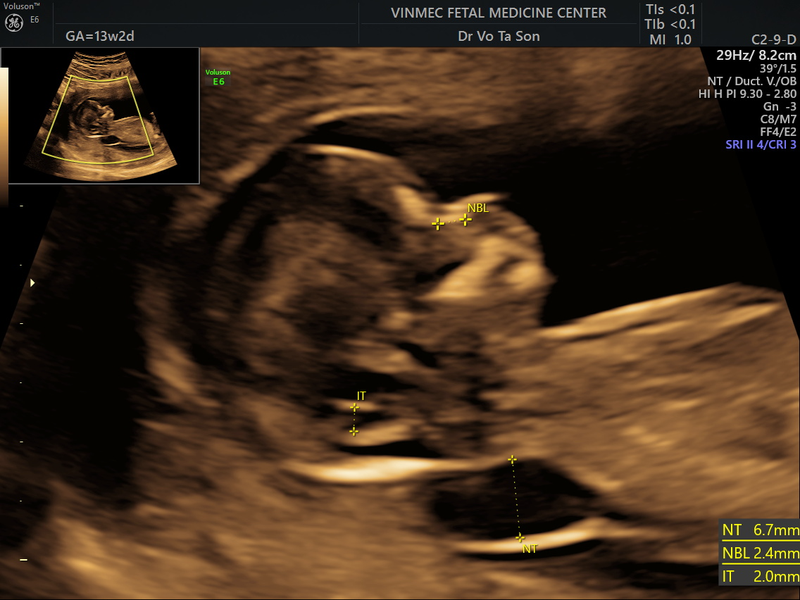

Đầu tiên, bác sĩ sẽ đo chiều dài của thai nhi từ đỉnh đầu đến cuối xương sống để xác định tuổi thai nhi. Tiếp theo, họ sẽ đo độ mờ da gáy bằng cách đo khoảng cách từ da đến phần dịch tích tụ sau gáy.

Kết quả đo độ mờ da gáy thường được đánh giá dựa trên các ngưỡng bình thường được xác định cho từng tuần thai cụ thể. Dưới đây là một số ngưỡng thường được sử dụng để đánh giá độ mờ da gáy:

Vậy độ mờ da gáy 1.8mm có bình thường không, chúng được coi là trong ngưỡng bình thường và không đáng lo ngại. Các nghiên cứu đã chỉ ra rằng độ mờ da gáy dưới 3.5mm thường có nguy cơ mắc hội chứng Down thấp. Do đó, với độ mờ da gáy 1.8mm, không có gì là quá lo lắng và nguy cơ mắc hội chứng Down cũng rất thấp.